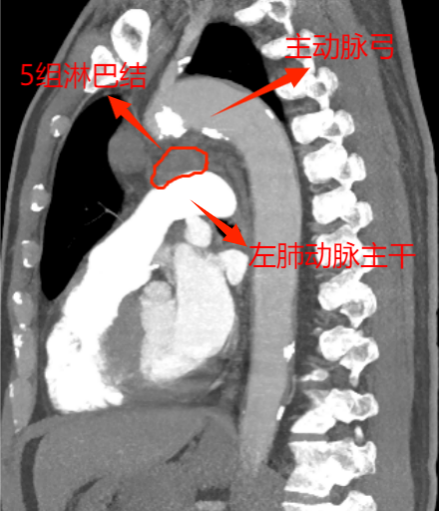

這下讓外科手術(shù)團隊為難了,因為兩組淋巴結(jié)臨近主動脈及左肺動脈2處大血管,位置深,即使CT引導下穿刺活檢,僅毫厘之差,仍大概率會出現(xiàn)大出血、氣胸,甚至危及生命,需緊急開胸,不活檢。由于轉(zhuǎn)移瘤性質(zhì)難定,影響后續(xù)方案的制定,家屬也很焦慮。

為實現(xiàn)更微創(chuàng),手術(shù)采取了單孔胸腔鏡技術(shù)。此次手術(shù),慶幸的是左肺與胸腔粘連不嚴重,但5、6組轉(zhuǎn)移淋巴結(jié)又硬又緊,與周圍組織界限欠清,尤其是5組淋巴結(jié),深埋進主動脈弓與左肺動脈根部,左主支氣管間,旁邊還有重要的迷走神經(jīng)及喉返神經(jīng)。血管損傷可能導致大量出血,神經(jīng)損傷可能造成聲音嘶啞、飲水嗆咳等并發(fā)癥。